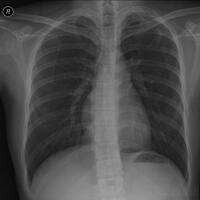

ini maksudnya nyuruh kita balapan sama SpPnya (atau SpPD-KP - pulmonologist-nya) atau gimana? btw, kalu ada file DICOM thorax fotonya, boleh tolong diupload? pusing liat JPG uy..ngga jelas. bukannya nyuruh balapan gan... tapi kesimpulan konsultasi dengan dokter spesialis paru & pernafasa